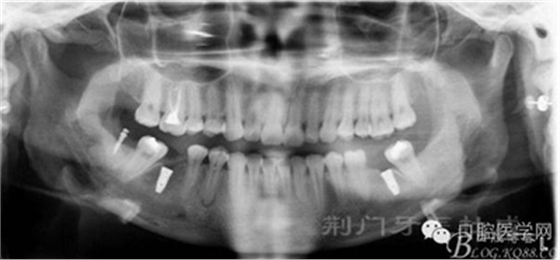

戴牙后忘記拍口內(nèi)照片了,只有一張X片,下次復(fù)診在補(bǔ)拍 44患者不愿冠修復(fù)

去除了支抗釘,要求患者3個(gè)月復(fù)查。